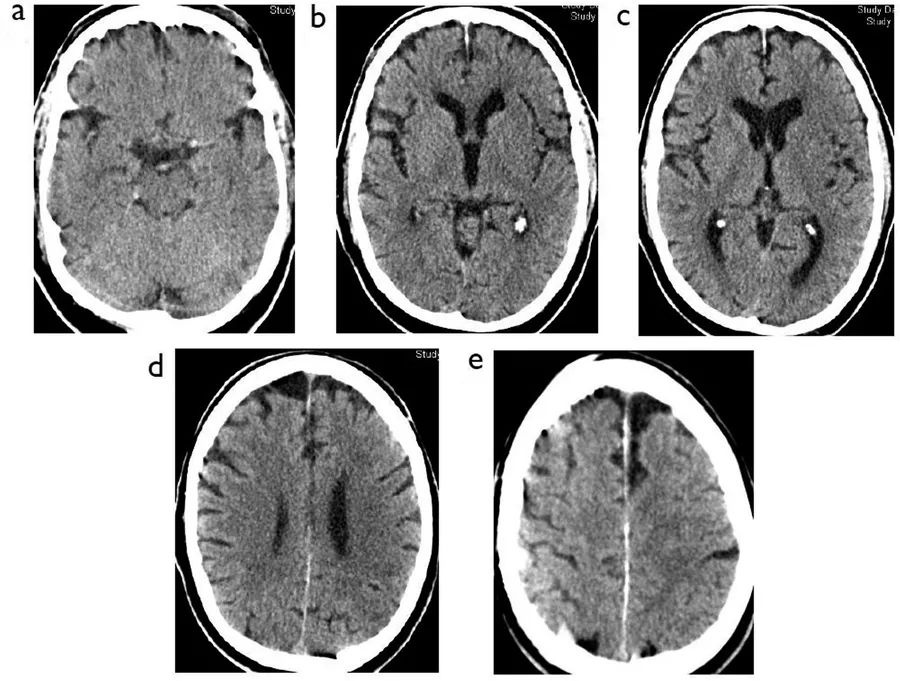

图4  81岁男性,既往房颤、2型糖尿病,缺血性卒中超急性期,卒中后1.5小时,NIHSS评分26分,A~E:就诊时CT;E~F:静脉溶栓2天后CT

患者就诊时的CT除了左侧颈内动脉末端的致密影之外,还可以看到岛叶密度降低,豆状核模糊,大脑中动脉供血区超过1/3的区域出现了模糊不清的稍低密度,左脑半球肿胀,脑沟消失。本例患者广泛的早期缺血性改变与脑水肿,使得溶栓或取栓术后的出血性转化风险显著上升。